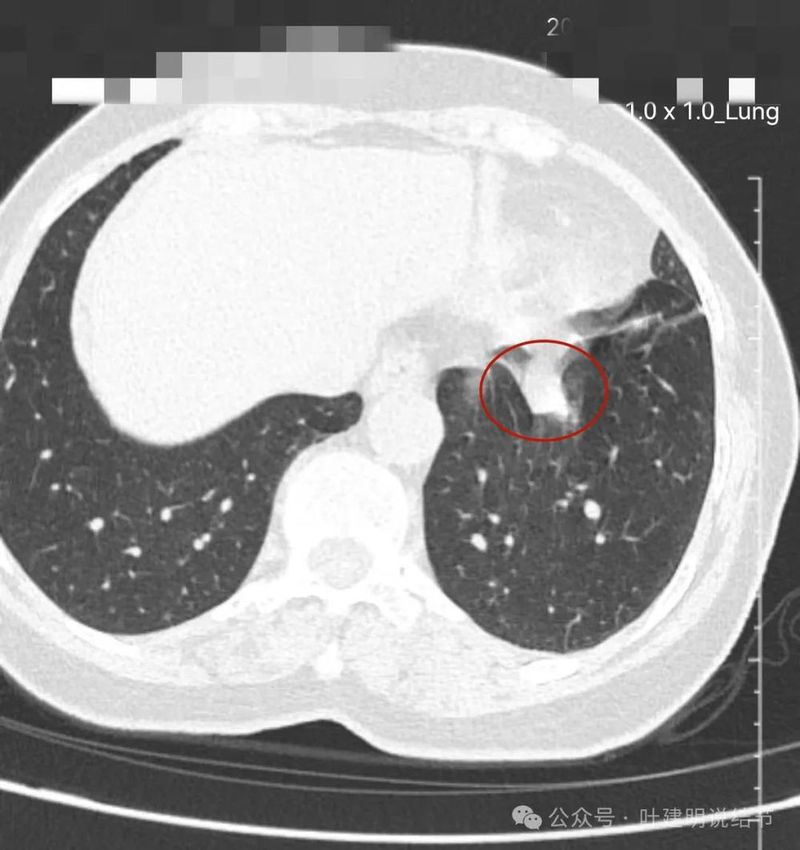

再看左下主病灶连续层面与重建影像:

冠状位见病灶与周围结构有间隙,说明不像炎性,如果是炎症,挨这么近,一般会搭牢的。